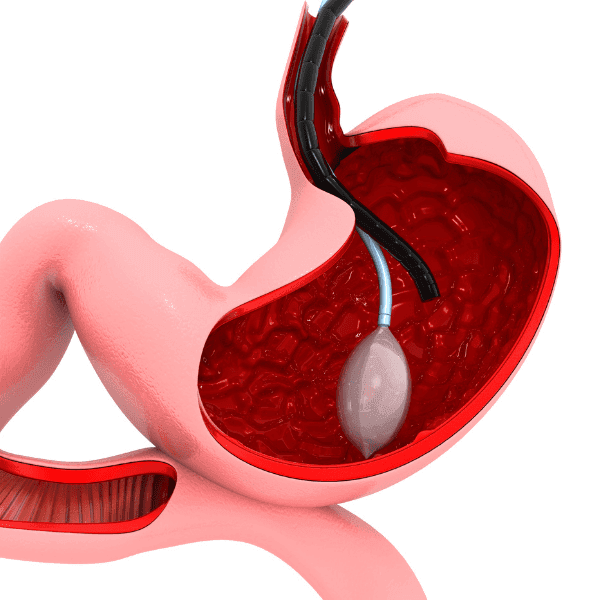

علاج السمنة بدون تدخل جراحي يعتمد على تقنيات مبتكرة تستهدف الدهون مباشرةً دون الحاجة إلى شقوق جراحية أو تخدير. تعتمد هذه الأساليب على استخدام أجهزة متخصصة مثل أجهزة التخسيس غير الجراحية التي تعمل على تفتيت الدهون وإزالتها بفعالية.

تتعدد تقنيات نحت الجسم، وكل تقنية لها مزاياها التي تناسب احتياجات الأفراد المختلفة. أبرز التقنيات المستخدمة هي:

نعم، بفضل التقدم التكنولوجي، أصبح التخلص من الدهون الموضعية بدون جراحة واقعًا يتيح للأفراد تحسين مظهرهم بسهولة وأمان. تُعد هذه الخيارات مثالية للتعامل مع الدهون العنيدة التي تقاوم الحميات الغذائية والتمارين الرياضية في مناطق مثل البطن، الأرداف، الذراعين، والفخذين.